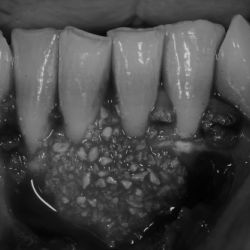

Caso de cirugía periodontal

Cirugía periodontal en un paciente